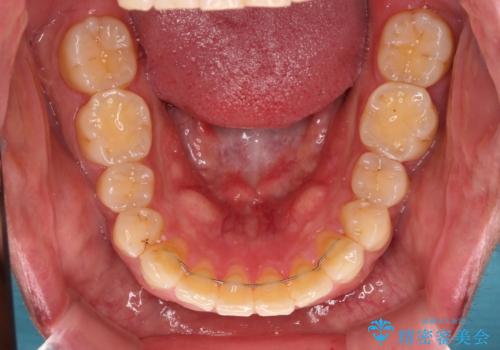

- 20代男性

- インビザライン

- 4年8ヶ月

- 前歯のデコボコを気にして来院された患者様です。

当院でインビザライン矯正治療をされている方からのご紹介ということで、インビザラインでの矯正治療をご希望でした。

ワイヤー矯正に比べ来院頻度は低いものの、新幹線での通院のため、やや治療期間が延びることが懸念されました。

配属異動や長時間勤務などによりインビザラインが十分に装着できない期間があり、インビザライン有効期限5年間ギリギリとなってしまいました。